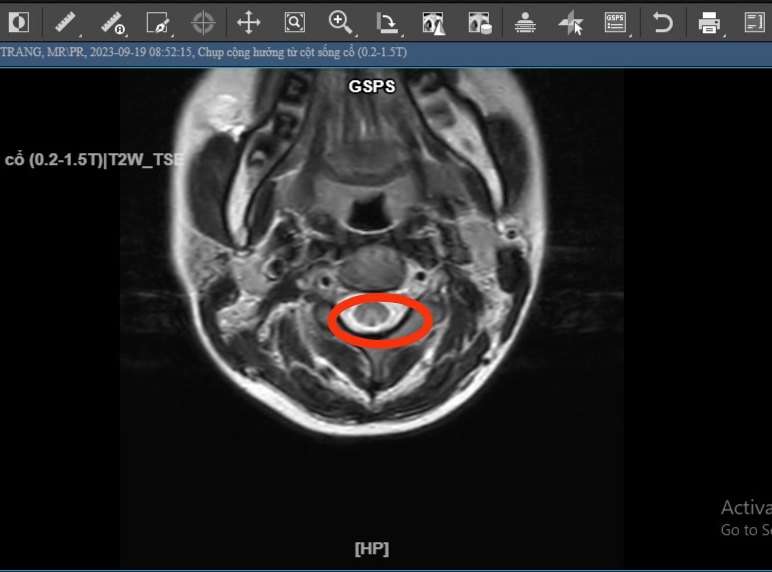

Hình ảnh tổn thương tủy cổ ngang từ C1 – T2 dấu “V” ngược

Sau khi làm các xét nghiệm cận lâm sàng, kết quả định lượng Homocystein của bệnh nhân tăng cao, Vitamin B12 giảm mạnh, chụp cộng hưởng từ cột sống cổ có hình ảnh tổn thương sừng sau tủy cổ. Căn cứ vào thăm khám lân sàng, cận lâm sàng, kết hợp khai thác thông tin người bệnh, bác sĩ đã chẩn đoán bệnh nhân bị tổn thương thần kinh tủy sống cổ, do ngộ độc khí cười N20.